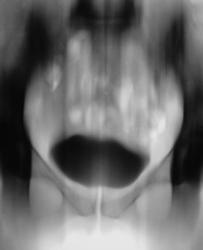

Почки контурируются в типичном месте, обычной формы и размеры. R-позитивных уроконкрементов в проекции мочевыносящих путей на обзорной урограмме не выявлено. ЧЛС контрастированы синхронно, не расширены. Мочеточники контрастированы, левый просматривается на всем протяжении, в нижней 1/3 незначительно стойко расширен, оттеснен кверху и вправо (хотя возможен такой вариант расположения устьев мочеточников - к сожалению правый мочеточник не визуализируется т.е. несчем сравнить). В мочевом пузыре, слева от срединной линии, дефект наполнения с четкой неровной границей.

Валентин Львович! Дефект наполнения мочевого пузыря слева имеется. Сказать вне пузырный или внутрипузырный сложно. Я бы выполнил УЗИ мочевого пузыря. Урологам порекомендовал бы цистоскопию.

Валентин Львович томограмки у вас хорошие получились, а как вы это расценили? Лично мне кажется это от давления из вне, а по поводу УЗИ, разве оно не входит в алгоритм обследования пациентов с МКБ и почечной коликой у вас в больнице?

Боли больше слева. Мне этот чертов дефект наполнения в мочевом пузыре тоже "не давал покоя".

У женщин часто так матка поддавливает мочевой пузырь

Мы решили сразу после исследования сделать томографию мочевого пузыря.